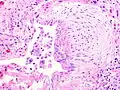

The histologic hallmarks of UIP, as seen in lung tissue under a microscope by a pathologist, are interstitial fibrosis in a "patchwork pattern", honeycomb change and fibroblast foci (see images below).[6] [7]

A fibroblast focus in a surgical lung biopsy of UIP. Hematoxylin-eosin stain, high magnification. The white space to the left is an airspace. The pale area to the right is a fibroblast focus. It is an area of active fibroblast proliferation within the interstitium of the lung.